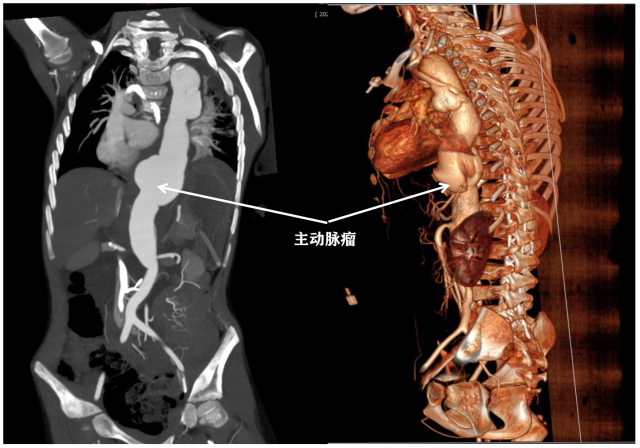

时隔四年他再发主动脉瘤,甚至引发了大面积的主动脉夹层。据家长回忆,今年8月2日,小泰突然出现持续性腹痛、呕吐,在当地三甲医院就诊。结合患儿病史,急诊医师第一时间予查CTA,结果提示主动脉夹层,肠系膜上动脉近段局部夹层,腹腔干起始部变窄,呈鱼钩样改变,提示正中韧带压迫综合征。

影像清晰显示主动脉瘤。 受访者供图

在当地医生的协助下,小泰于8月4日转入了广东省人民医院。入院时,患儿呼吸急促、心率快、血压高,该院PICU(儿科重症监护室)救治小组予行降压和控制心率的治疗,并在最短的时间内完成了心脏彩超和动脉全程CTA检查,提示广泛型主动脉夹层(DeBakey III型、Stanford B型),降主动脉下段-腹主动脉上段周围血肿。这意味着降主动脉破裂、腹主动脉夹层动脉瘤先兆破裂,已经出现局限性压迫,随时有大出血、休克、心脏骤停等风险,手术救治迫在眉睫。